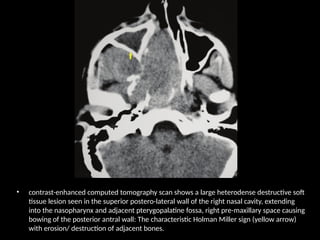

• contrast-enhanced computed tomography scan shows a large heterodense destructive soft

tissue lesion seen in the superior postero-lateral wall of the right nasal cavity, extending

into the nasopharynx and adjacent pterygopalatine fossa, right pre-maxillary space causing

bowing of the posterior antral wall: The characteristic Holman Miller sign (yellow arrow)

with erosion/ destruction of adjacent bones.

• contrast-enhanced computedtomography scan shows a large heterodense destructive soft tissue lesion seen in the superior postero-lateral wall of the right nasal cavity, extending into the nasopharynx and adjacent pterygopalatine fossa, right pre-maxillary space causing bowing of the posterior antral wall: The characteristic Holman Miller sign (yellow arrow) with erosion/ destruction of adjacent bones.